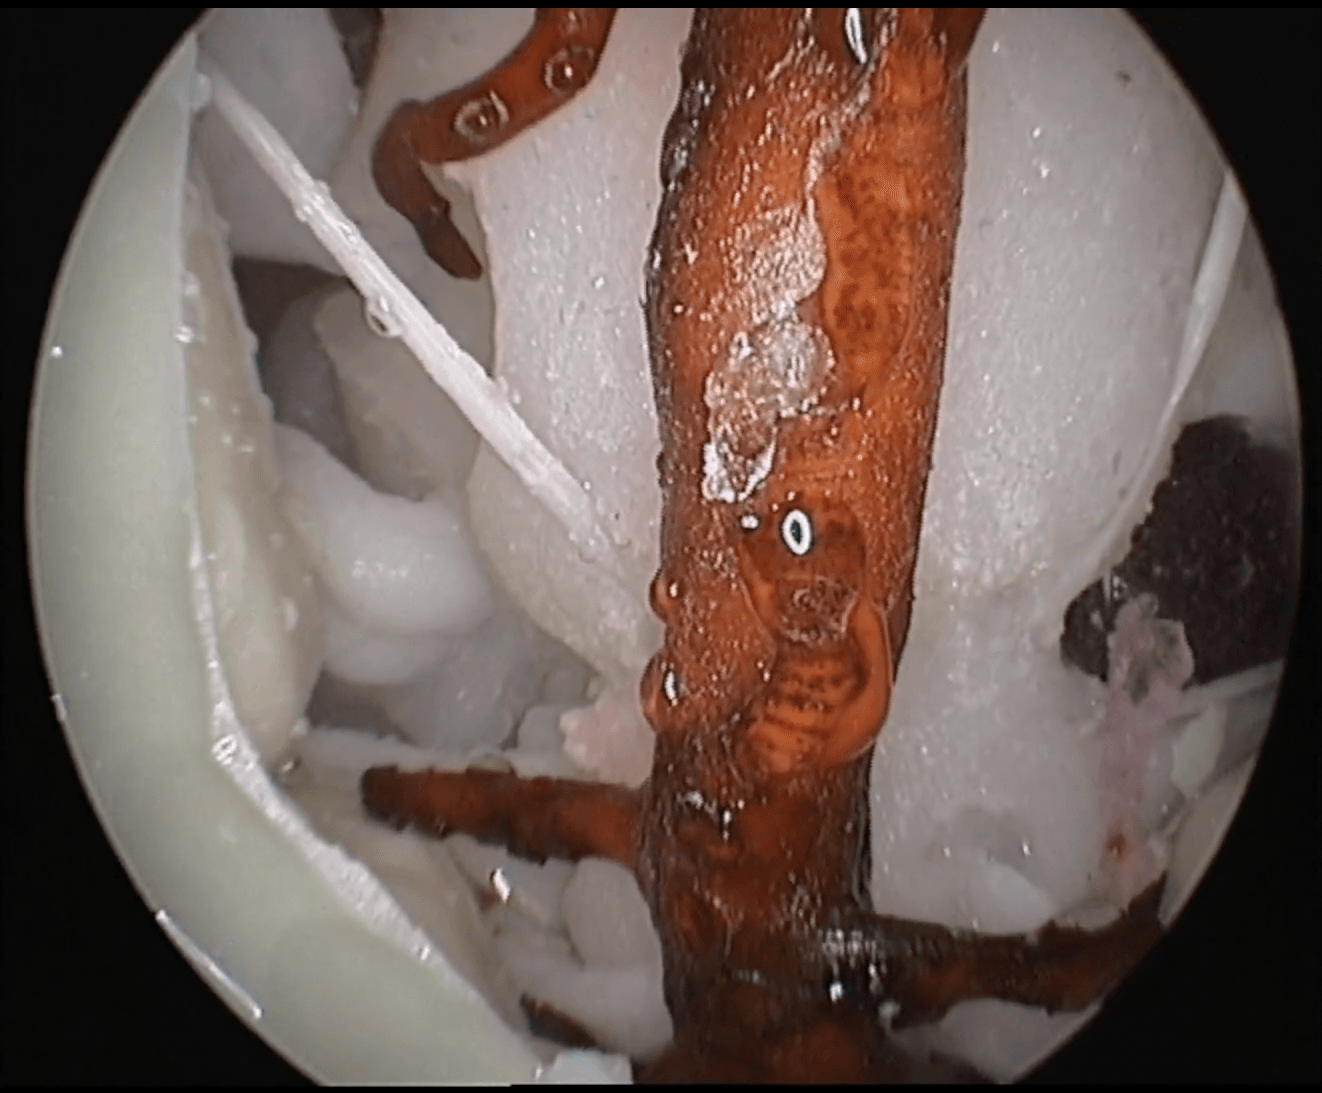

Advanced endoscopic transphenoidal surgery simulator.

Human skull with all the craniometric points, fissures and canals. 1:1 scaled from a real human CT scan with similar drilling properties to the human bone. Includes skin, nasal mucosa, turbinates, septum, as well as a detailed intrasphenoidal anatomy.

The inner skull is covered with dura, and includes all cranial nerves, intracranial arteries as well as the brain, cerebellum and brainstem. Pathology included: pituitary adenoma and planum sphenoidale meningioma extracted from real cases and including the DICOM images for the preoperative planning.

Expand your endonasal surgery in the sagittal and coronal planes to gain space, and enjoy the anatomical journey!